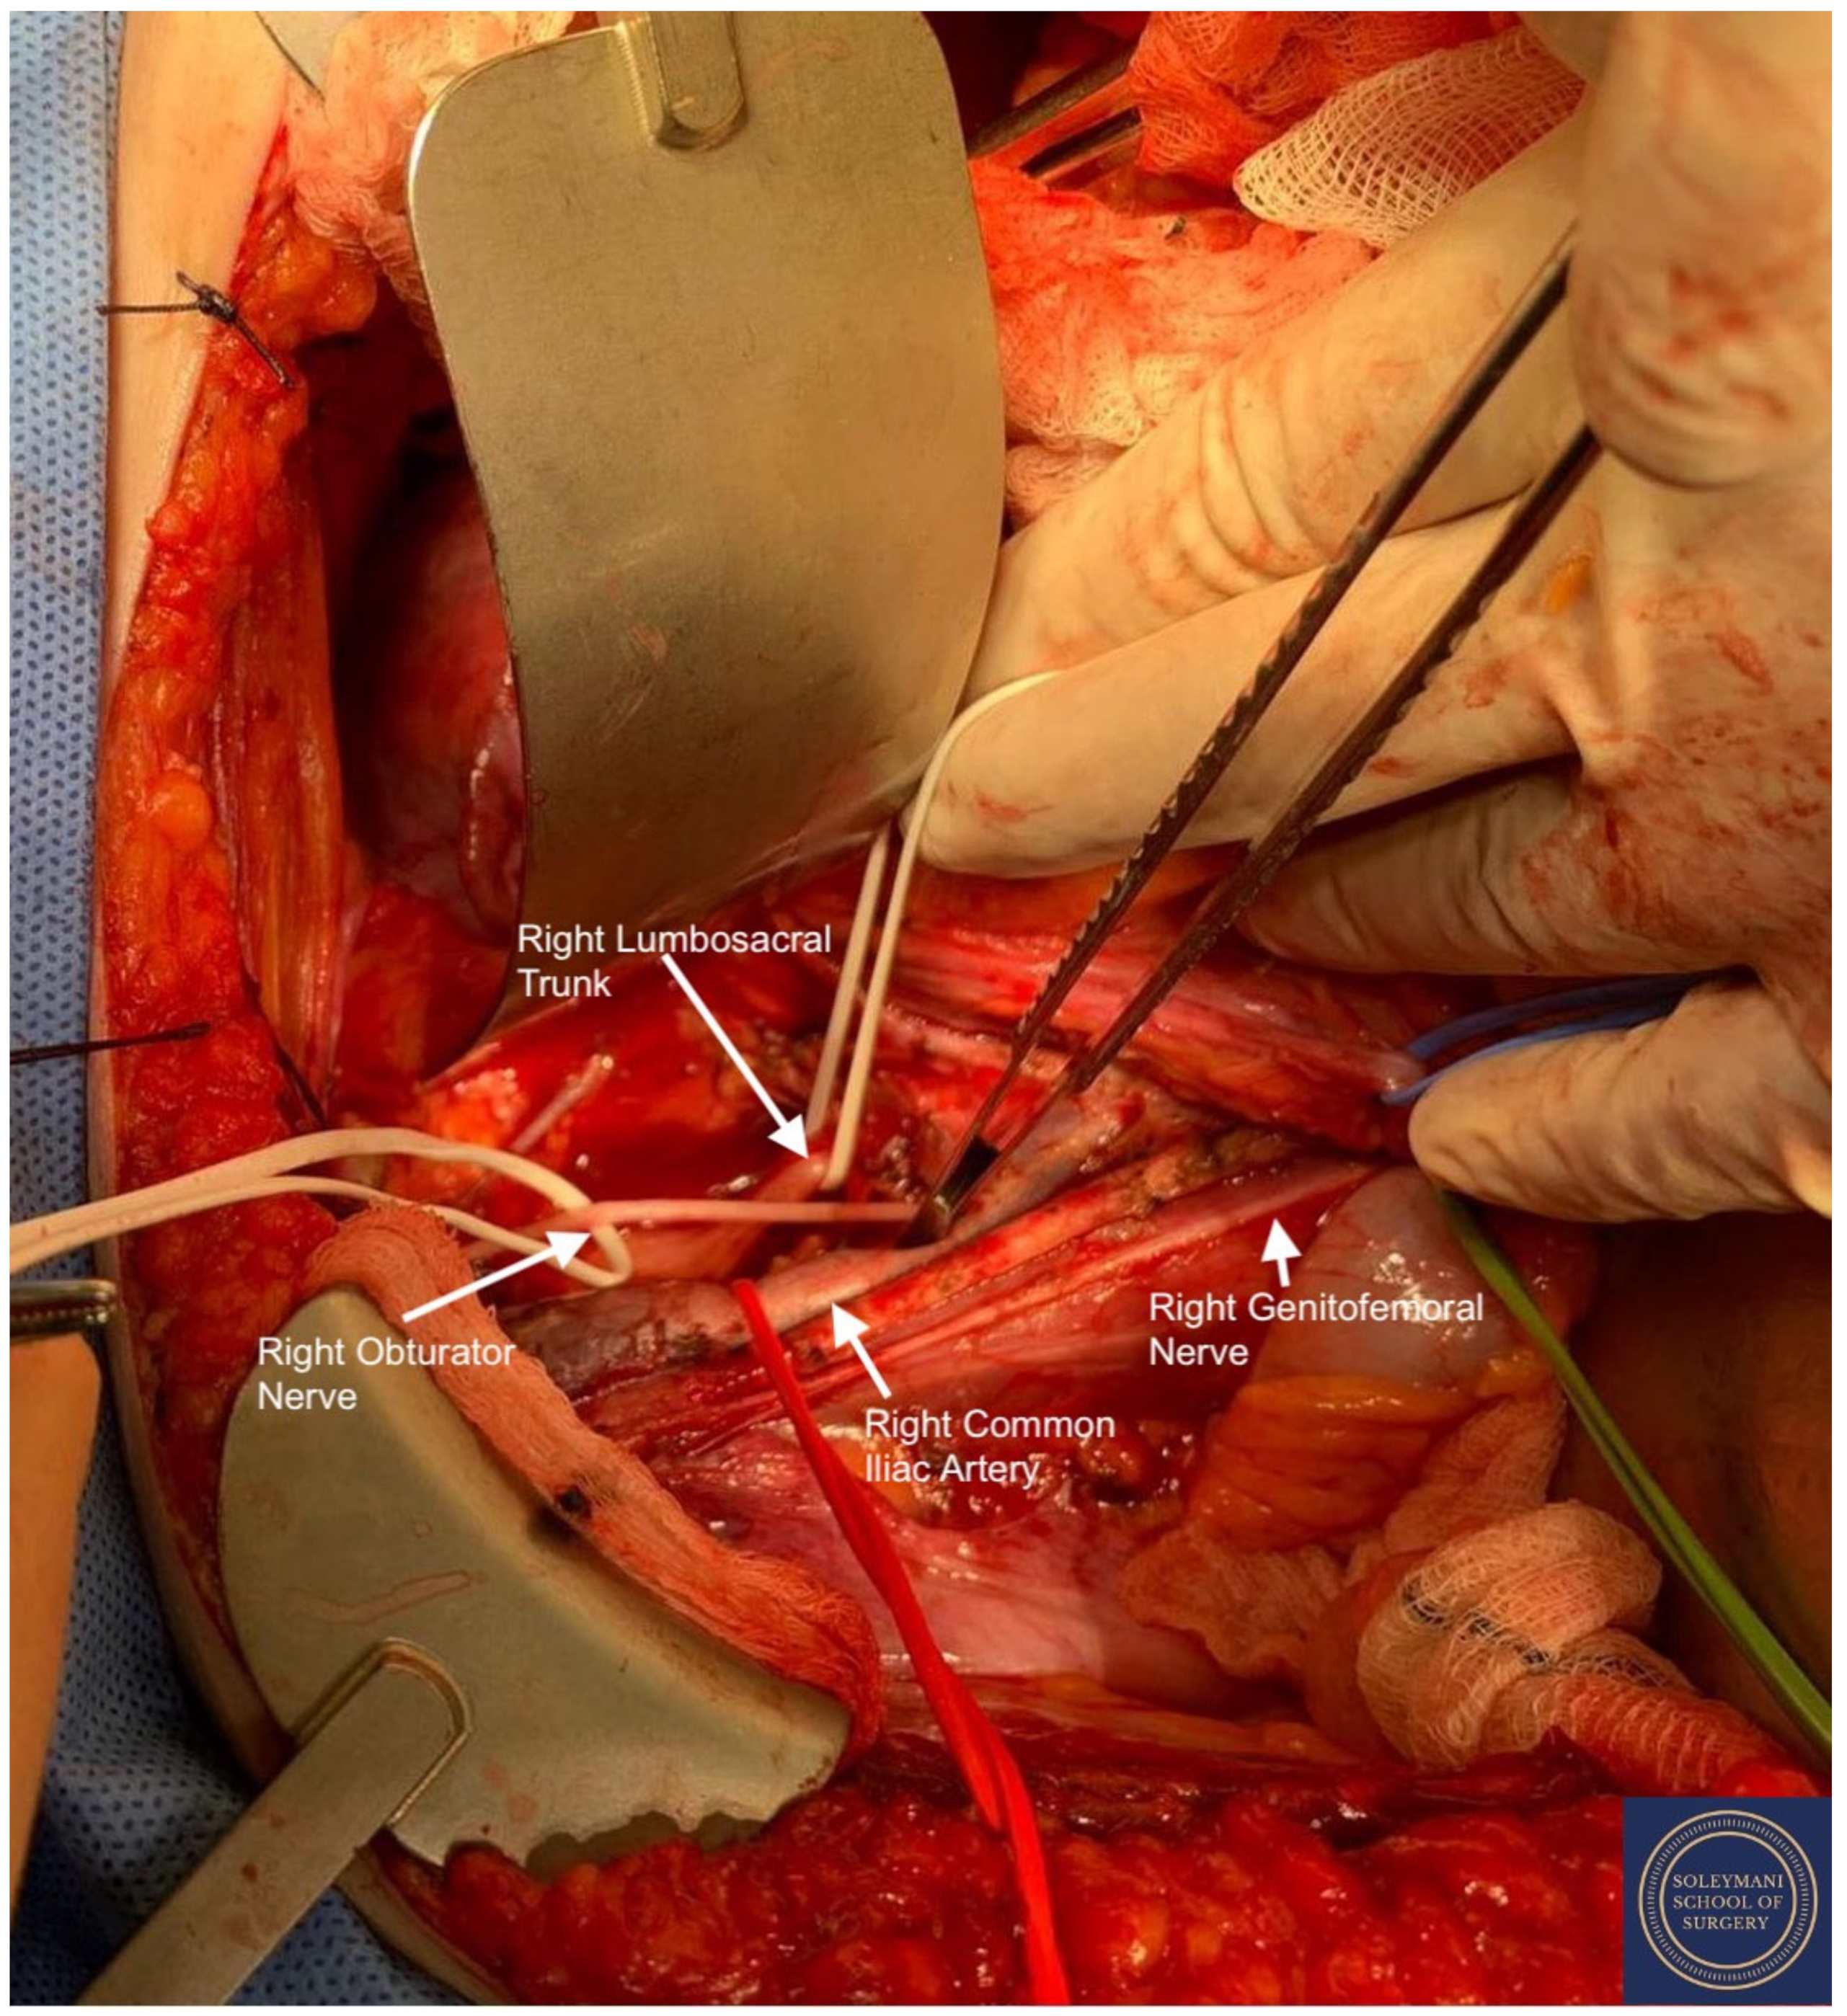

- The pararectal spaces were developed with exposure and preservation of the hypogastric nerves adhering medially to the mesorectum up to the level of the inferior hypogastric plexus and vein aergentis. The external iliac and obturator lymph nodes of the anterior pelvic compartments (Figure 6) were removed by completely stripping the external iliac artery and vein and removing the paravisceral pelvic fat pads, obtaining exposure of the obturator nerve, obturator artery and vein, the arcus tendineus, and proximal sciatic nerve (Figure 7 and Figure 8).

- Pelvic lymph node dissection was continued in the posterior compartment by removing all lymph nodes and fatty tissue around the internal and common iliac vessels, exposing the proximal pelvic obturator nerves and the lumbar rami of the sacral plexus. Para-aortic lymph node dissection was subsequently completed up to the level of the renal veins.